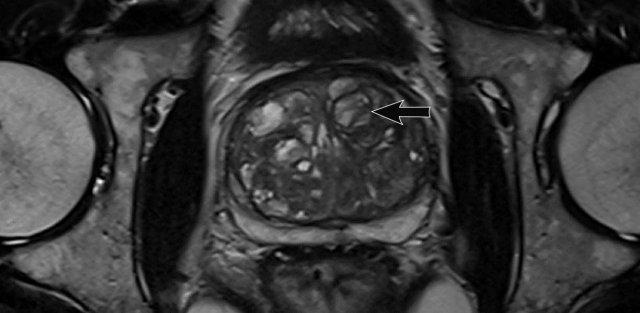

Tăng sản lành tính tuyến tiền liệt (BPH) dẫn đến sự hình thành các nốt có bờ rõ, có vỏ bao trong vùng chuyển tiếp.

Một số nốt này có mô đệm đặc với tín hiệu thấp trên chuỗi xung T2W và ADC thấp (mũi tên vàng).

Đặc điểm quan trọng nhất để phân biệt các nốt BPH với ác tính là hình thái thường có bờ rõ và giới hạn rõ ràng, được đánh giá trên các chuỗi ảnh axial, coronal và sagittal.

Tổn thương vùng ngoại vi bên trái được phân loại PI-RADS 5 (mũi tên đỏ).

Sinh thiết có hướng dẫn MRI cho thấy Gleason 3+4.

Các nốt BPH giảm tín hiệu T2 có thể có bờ kém rõ hơn trong vùng chuyển tiếp và có thể biểu hiện mức độ khuếch tán hạn chế nhất định.

Ngoài ra, các nốt này có xu hướng ngấm thuốc sớm và mạnh trên DCE, khiến việc phân loại dứt khoát trở nên khó khăn.